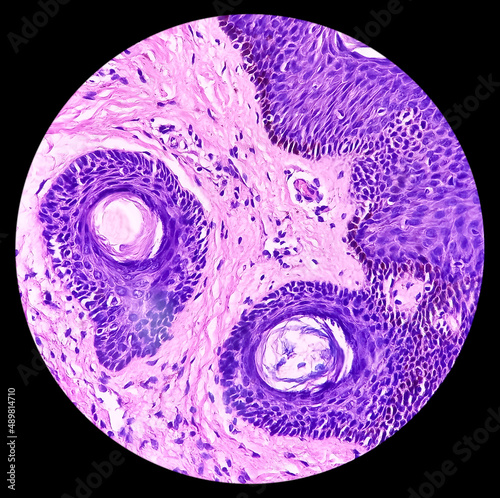

Mikrofotografi - Plakater, Poster, Billeder på lærred